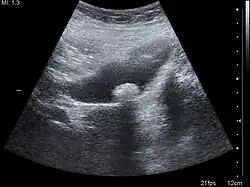

Ein Binnenecho bezeichnet in der medizinischen Ultraschalldiagnostik Muster unterschiedlicher Echogenität innerhalb einer anatomischen oder pathologischen Struktur, die durch unterschiedliche Reflexionen verschiedener Gewebearten entstehen. Die Analyse von Binnenechos ist ein wichtiges diagnostisches Werkzeug in der medizinischen Bildgebung.[1] Am häufigsten wird der Begriff für Muster innerhalb einer sonst echofreien Struktur, also flüssigkeitsgefüllten Gebilden wie Zysten und Hohlorganen, verwendet.[2] Abweichungen von der normalen Echogenität können dabei ein ganzes Organ betreffen und werden als schwach, stark oder fehlend eingestuft. Sie können aber auch nur in einem Herd (unifokal) oder in vielen Herden (multifokal) auftreten. Letztere gehen dann häufig in das normale Bild eines Organs über, man spricht dann von einem inhomogenen Binnenecho.[3]

Binnenechos sind Hinweise auf die Struktur des Befundes. Maligne Tumoren weisen häufig ein grobes Binnenecho auf. Man erkennt hier zum Beispiel eine inhomogen-echoarme Binnenstruktur. Dabei ist ein Binnencho aber selten ein sicheres diagnostisches Kriterium. So können Organerkrankungen auch gänzlich ohne Veränderungen des Binnenechos einhergehen.[3] Schilddrüsengewebe, Gallensteine[4] oder unterschiedliche Tumortypen[5] können ein starkes, ein schwaches oder kein Binnenecho aufweisen.